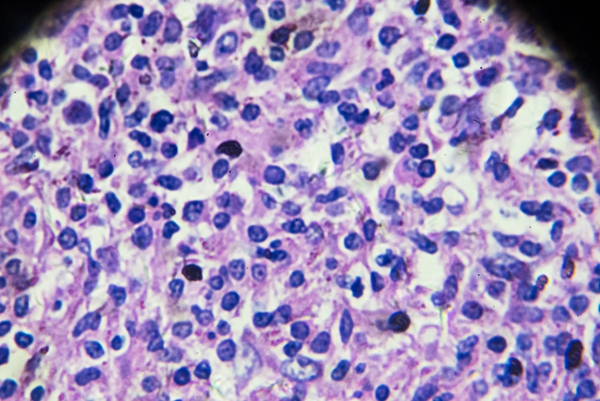

HIV 是一种能攻击人体免疫系统的病毒,它把人体免疫系统中最重要的 CD4T 淋巴细胞作为主要攻击目标,大量破坏该细胞,使人体丧失免疫功能,从而易于感染各种疾病,并可发生恶性肿瘤,病死率较高。